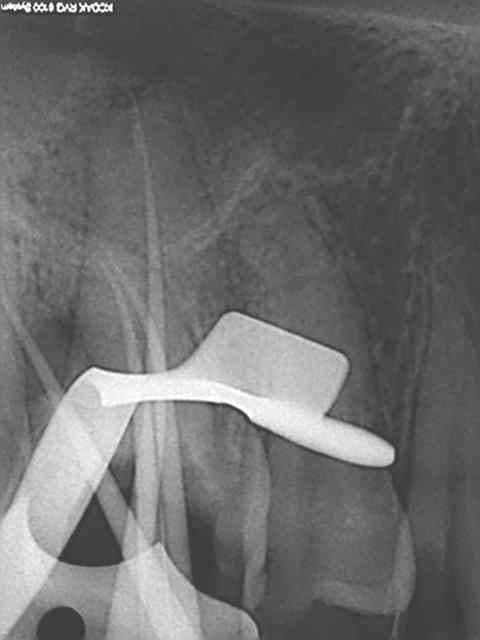

rte sur 16 au r25 un bonheur, le mv2 était imperméable au sx et s1 le r25 n'en a fait qu'une bouchée!

> rte sur 16 au r25 un bonheur, le mv2 était imperméable au sx et s1 le r25 n'en a

> fait qu'une bouchée!

C'est vrai, mais attention quand tu commences à faire des rte au reciproc tu te mets forcément à forcer un peu. La plupart du temps ça marche, et puis parfois ça fait de belles perfos !

Je ne l'utilise plus qu'au niveau apical sur les rte pour débloquer certaines situations.